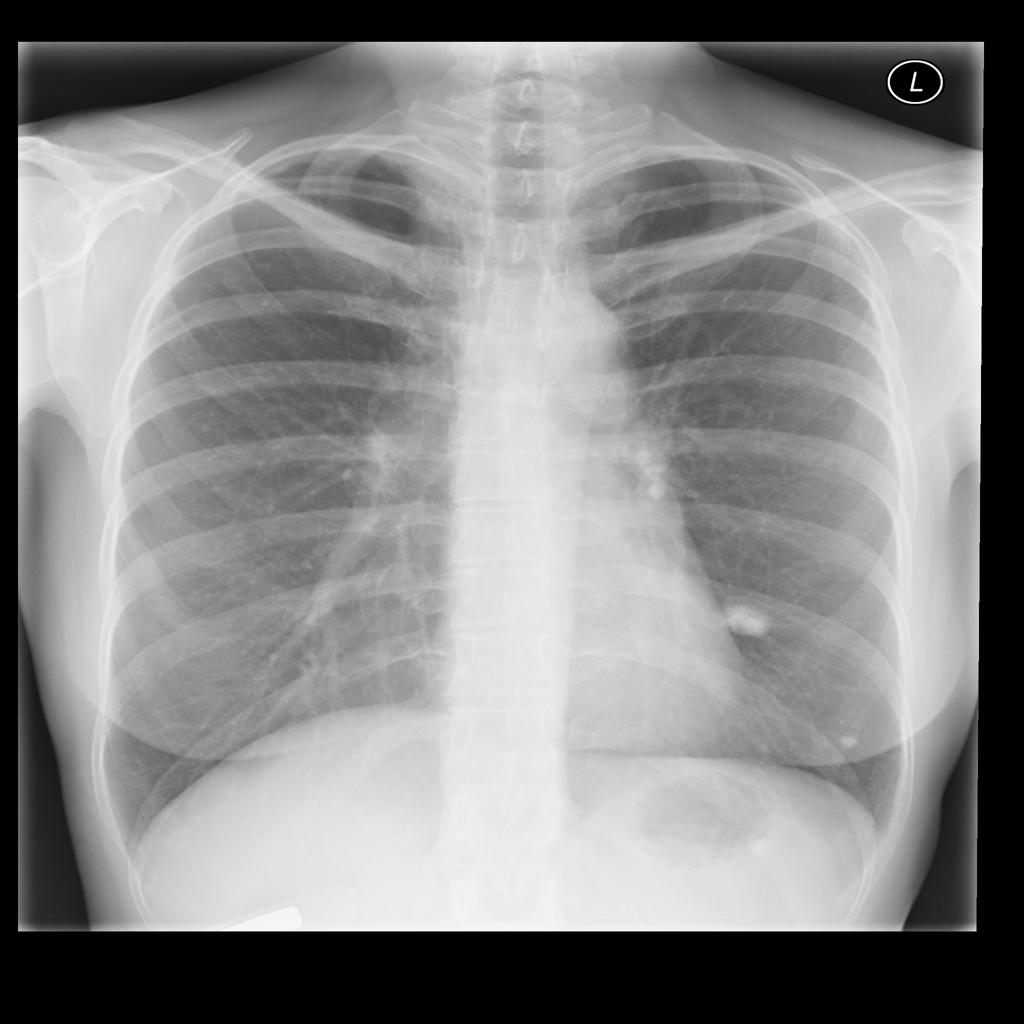

Nodule

A nodule is a small rounded opacity in the lung or chest field. It is a descriptive imaging finding that can be benign or more concerning depending on size, appearance, and context.

Showing up to 90 reference images for Nodule.

PAT-250B · IMG-000Nodule

PAT-250B · IMG-000

PA